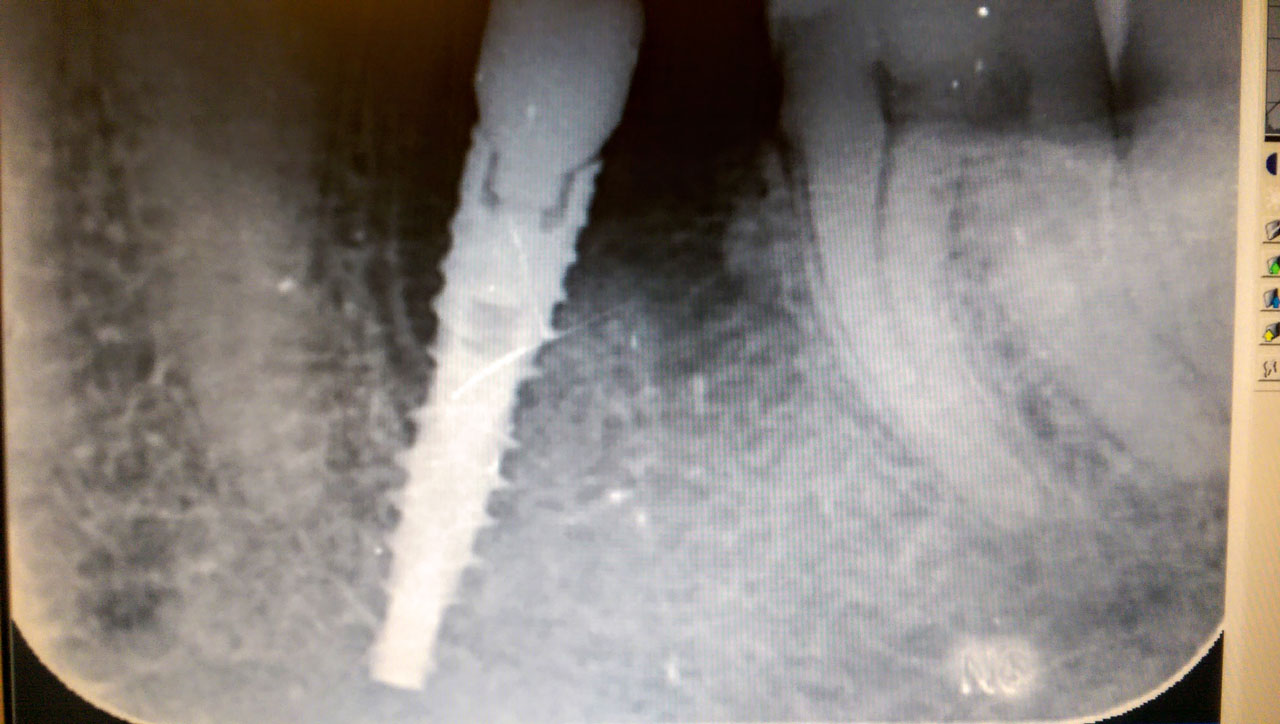

Alsó állcsont teljes rehabilitációja 72 óra alatt

Alsó állcsont teljes rehabilitációja 72 óra alatt, azonnal terhelhető implantátumokkal súlyos paradontitisben szenvedő dohányzó páciens esetében. Az alsó állcsont fogai mind mozogtak az előrehaladott fogágypusztulás miatt.

A fogakat eltávolítottuk, a gyulladt, fertőzött csontot kitakarítottuk, kifertőtlenítettük, majd azonnal implantáltunk.

Svájci, IHDE márkájú, azonnal terhelhető implantátumokat helyzetünk be, és ezekre harmadnapra rögzített, hosszútávú, fémvázas, esztétikus műanyaggal leplezett hidat ragasztottunk be.

Ezt az ideiglenes hidat a sebek gyógyulása miatt használjuk, de tartóssága miatt véglegesként is használható. A legtöbb esetben, ahogy itt is, 6 hónap múlva porcelán hídra cseréljük, a teljes gyógyulás után.